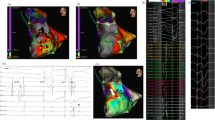

Substrate map data analysis is summarised in Table 3. There was a significant reduction in the average bipolar BZA of 4.4 cm2/12% (p = 0.026) and bipolar LPA of 3.5 cm2/83% (p = 0.0449) post-ablation. Figure 2a shows representative substrate and LP maps pre- and post-ablation. There was a significant reduction in the mean bipolar (0.14 mV (p = 0.0007)) and unipolar (0.59 mV (p = 0.0072)) voltages of the ATA post-ablation with Fig. 2b highlighting the reduction in signal attenuation from the DTA catheter. Complete procedural success was achieved in 9 procedures. No post-ablation stimulation protocol was performed at the end of 1 procedure due to a steam pop occurring after 48 min of ablation resulting in pericardial tamponade requiring drainage.

Representative case. Substrate and LP maps are shown in a representative case pre- and post-ablation, using standard LV bipolar voltage criteria, with the ATA highlighted with the dashed white line. Post-ablation, the BZA has been effectively reduced from 7.5 to 3.2 cm2 with a corresponding increase in the DSA. The pre-ablation LPA (5.8 cm2) has been completely eliminated. The mean bipolar voltage of the ATA pre-ablation was 0.43 mV and effectively reduced to 0.36 mV post-ablation. b Electrogram amplitude attenuation of the bipolar LP signal from the DTA distal high-resolution electrode is shown (LP = late potential; ATA = ablation target area; BZA = borderzone area; DSA = dense scar area)